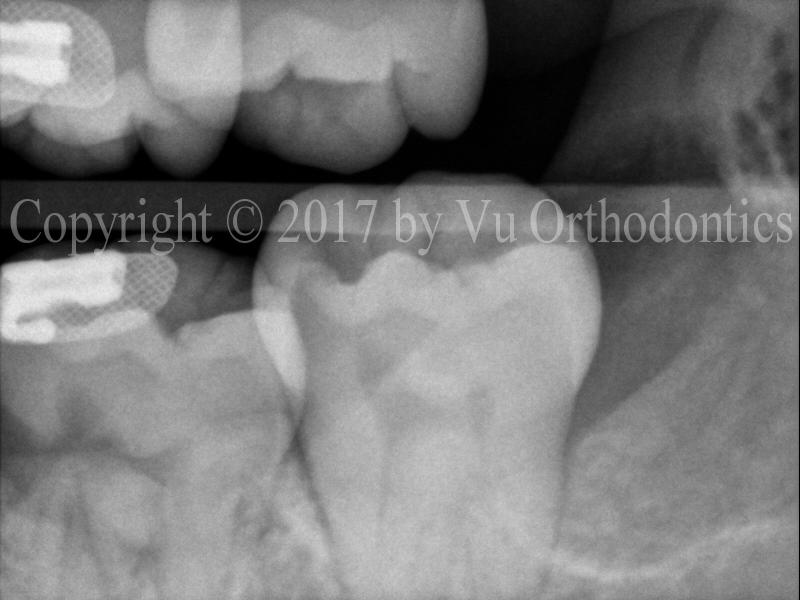

Figure 2 shows the result of impacted wisdom tooth #17 corrected after orthodontic treatment.

Fig. 2 Wisdom tooth #17 corrected by orthodontics (near the end of the treatment)